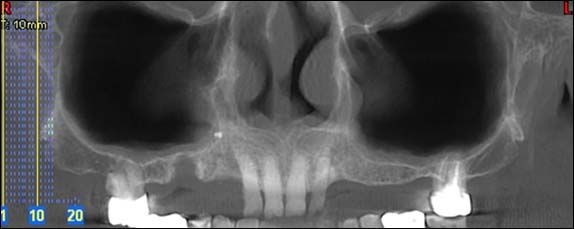

PANORAMIQUE :

Cette radio permet d’appréhender l’ensemble de votre dentition et des structures adjacentes.

Reconstruction panoramique